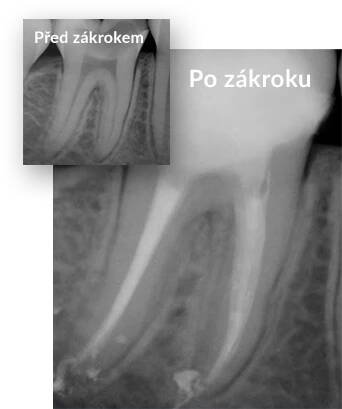

Fotka s případovou studií před-po. Na první force je vidět zub s nezaplněným kořenovýcm systémem a na druhé je vidět zub s dokonale zaplněným kořenovým systémem.